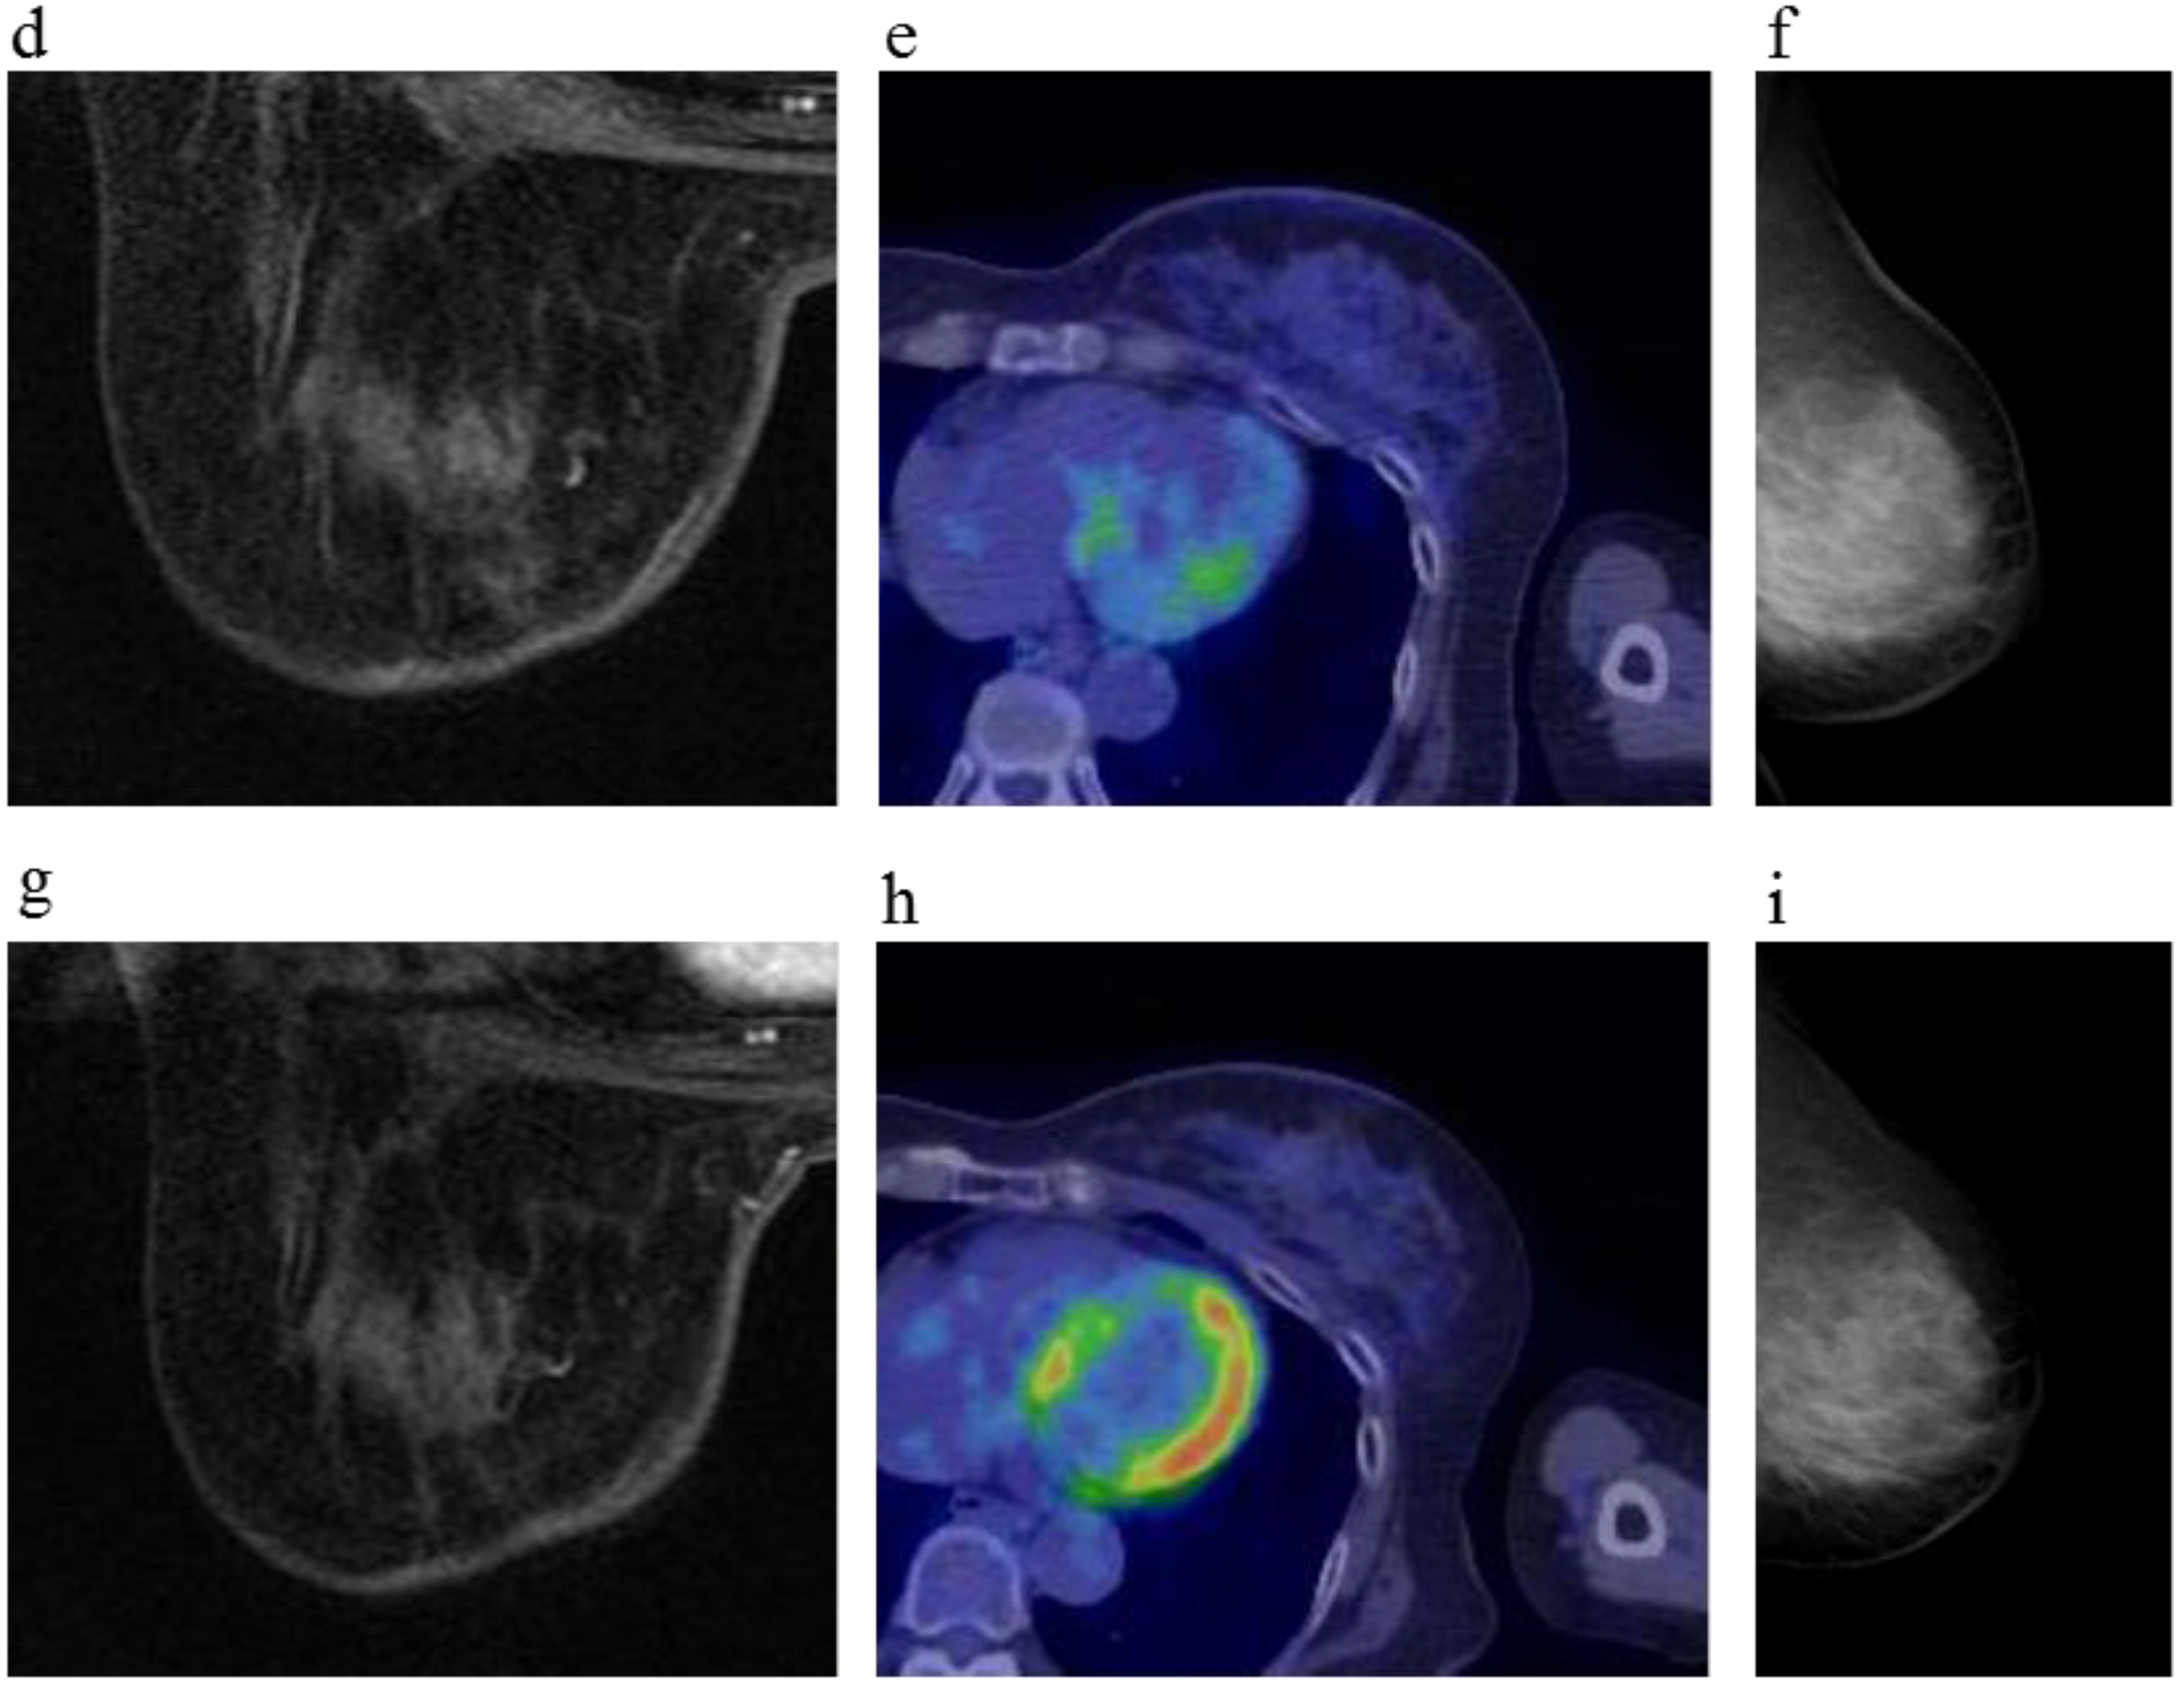

Figure 3.

A 81-year-old female (case 7 in Table 1, Table 2 and Table 3) with right breast cancer (cT2N1M0). CE breast MRI, PET-CT and mammography revealed a breast tumor before KORTUC II therapy, the region of tumor was 25 mm in large diameter (a–c); At the initial examination after the completion of KORTUC II treatment, the tumor was undetectable on PET-CT and mammography (e,f); On the other hand, the residual tumor was still recognized on breast CE MRI ((d): arrows). However, complete response was eventually achieved and no recurrence was identified on final examinations of all of these three diagnostic modalities (g–i).